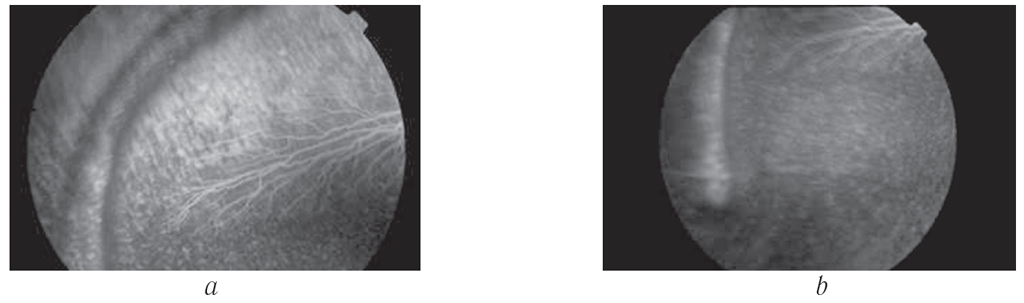

На 20-е сутки после операции проводили флуоресцентное ангиографическое исследование. По результатам флуоресцентной ангиографии перфузия сосудов сетчатки и сосудистой оболочки нарушена не была, кровоснабжение в области дренажного имплантата не изменено, иные патологические феномены не регистрировались (рис. 8).

Рис. 8. Картина флуоресцентной ангиографии на 20-е сутки после оперативного вмешательства: а — артериовенозная фаза; b — венозная фаза рециркуляции

Fig. 8. Fluorescein angiography on Day 20 after surgery: а – arteriovenous phase; b – venous recirculation phase